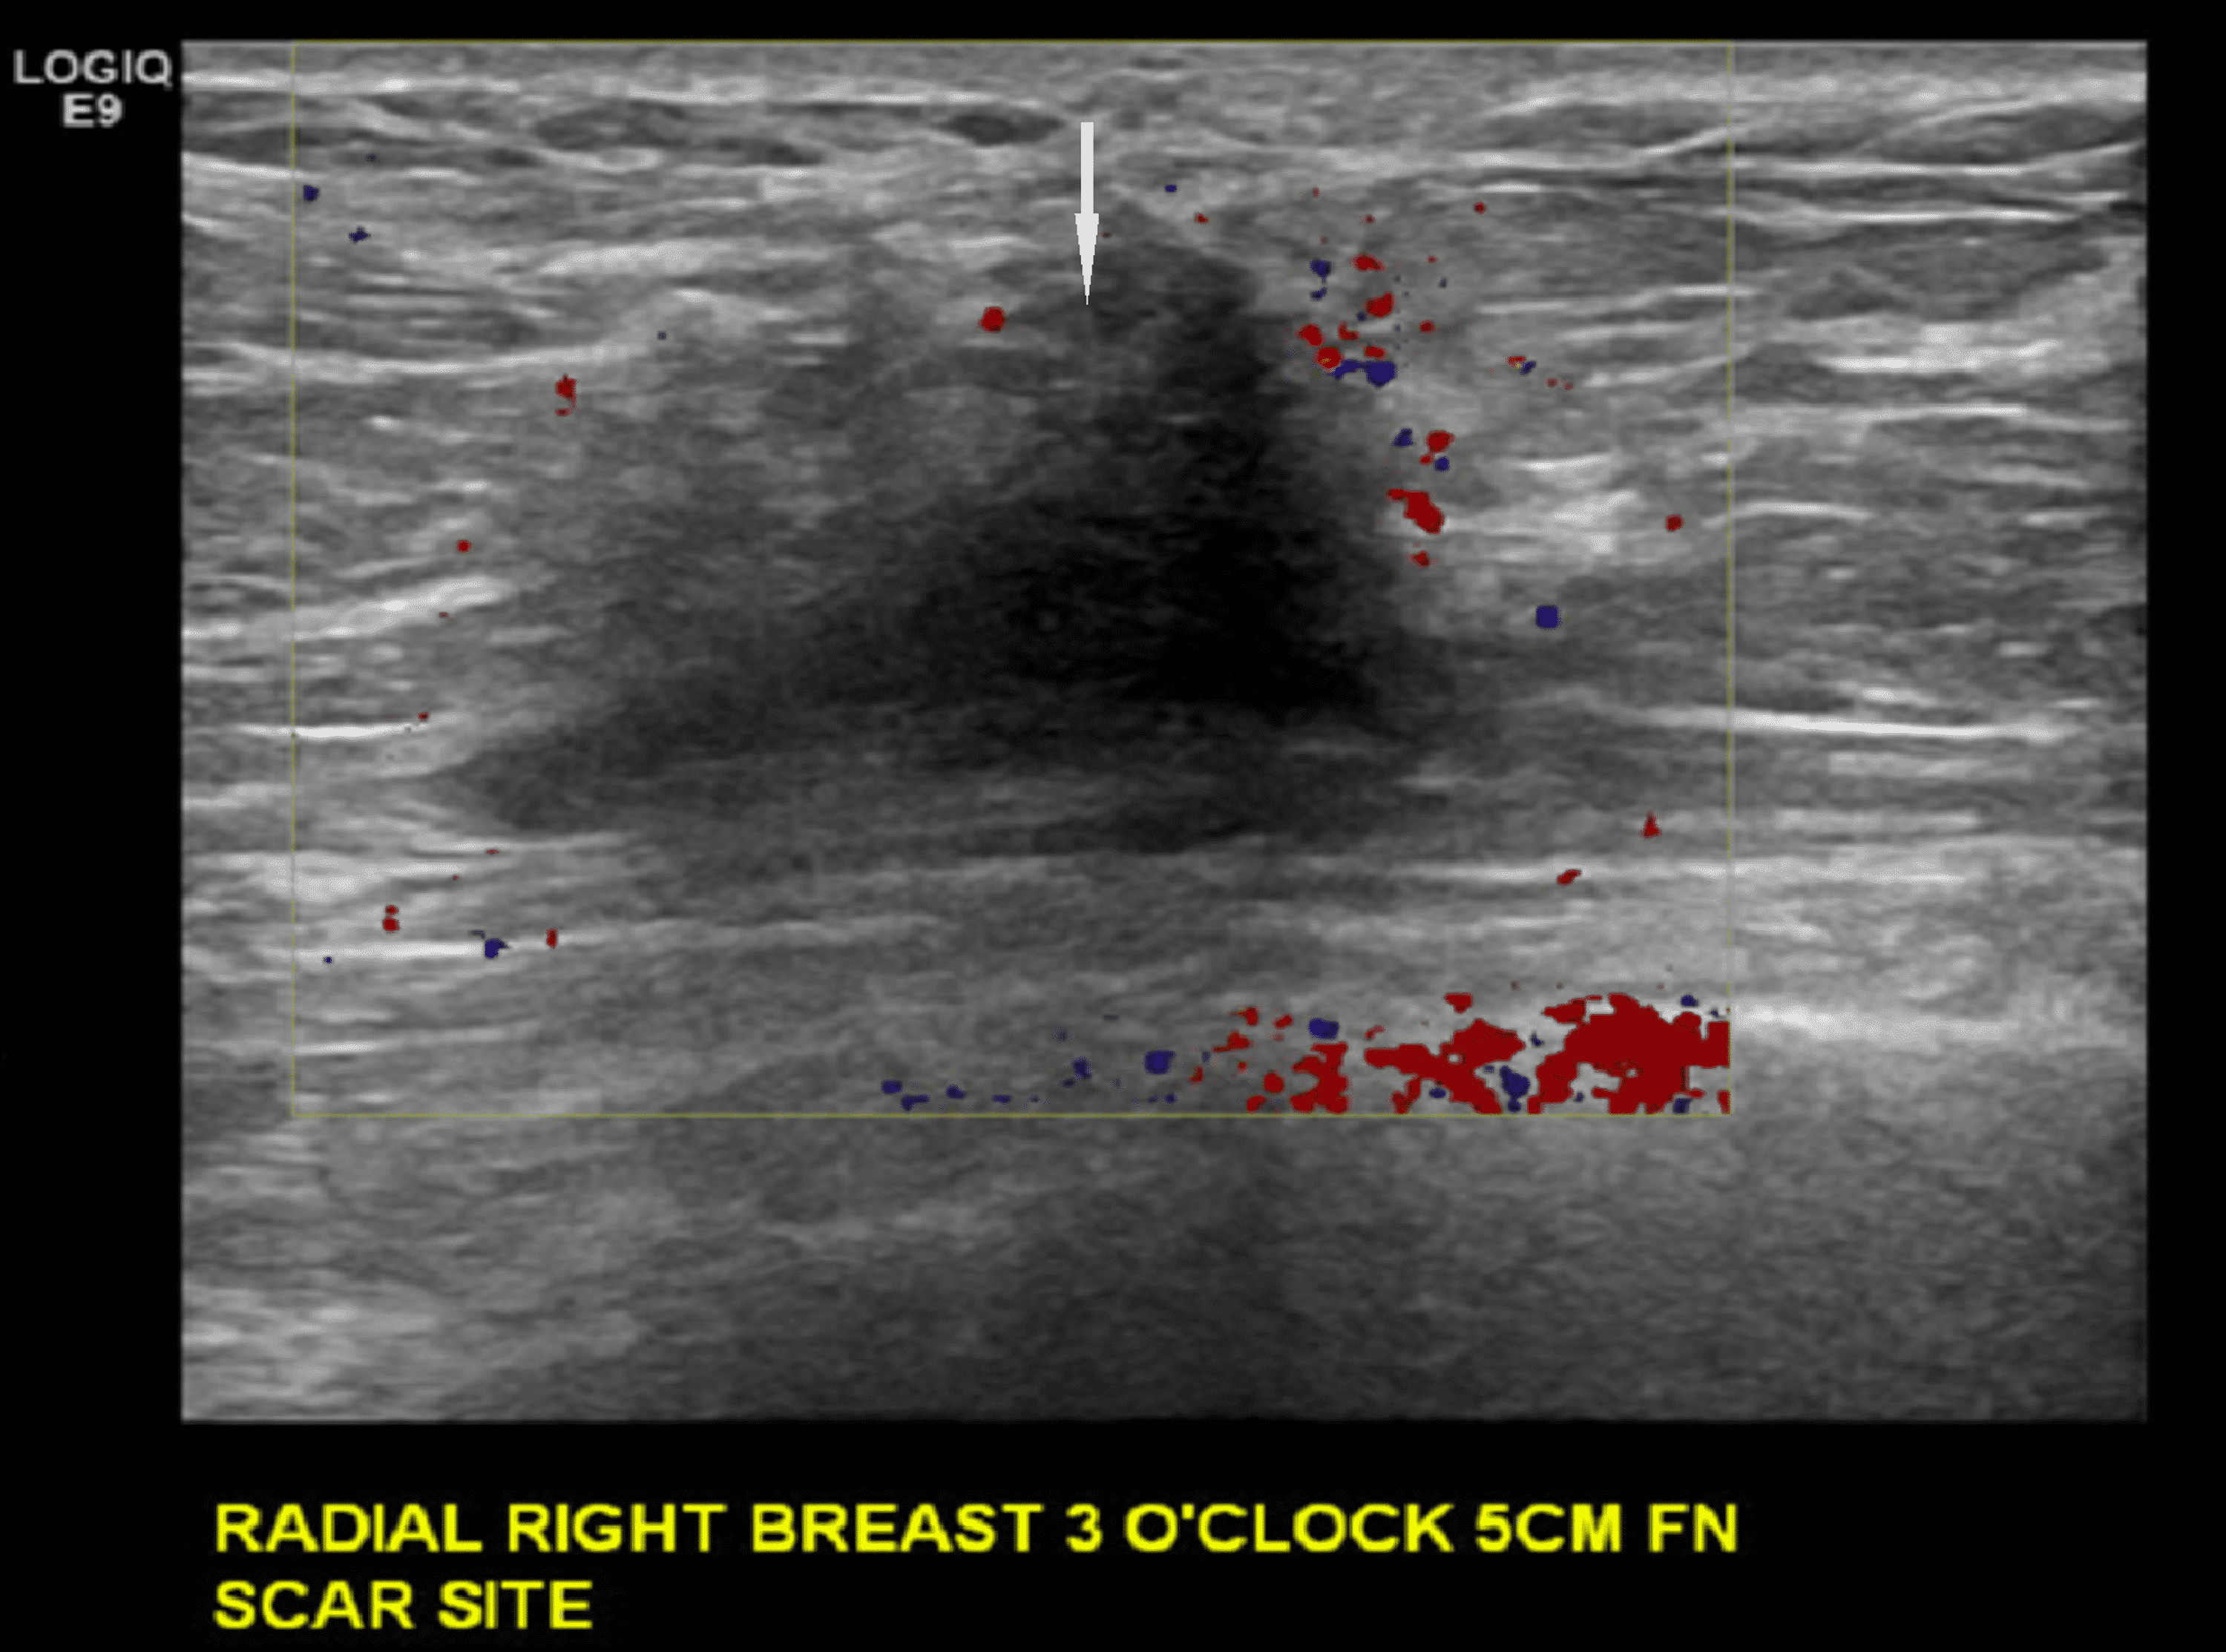

Cureus Invasive Lobular Cancer Arising in a Surgical Scar From Pain In Breast Cancer Scar scarring caused by breast cancer treatments can be distressing. Pain in the shoulder or. it can be difficult to know how your breast or scar area should feel, especially as the area can change over time as it repairs and. no, you don't have to accept pain and discomfort as a part of your daily life after. Pain In Breast Cancer Scar.

Cureus Invasive Lobular Cancer Arising in a Surgical Scar From Pain In Breast Cancer Scar Pain in the shoulder or. Pain and tingling in the chest wall, armpit, and/or arm. scarring caused by breast cancer treatments can be distressing. while pain is common and expected early in the recovery after surgery, some people may have pain that lasts for. the scar may be painful, tender and itchy. it can be difficult. Pain In Breast Cancer Scar.